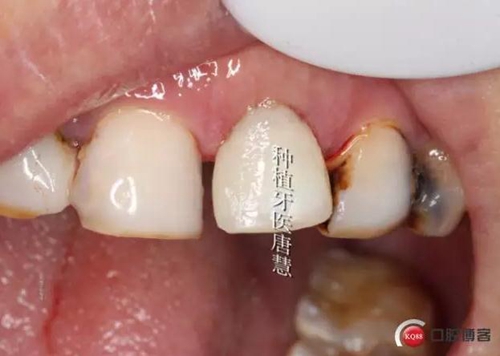

完成臨時修復(fù)

8.jpg